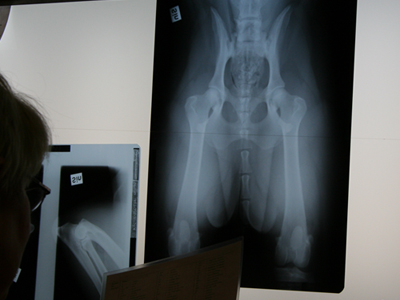

Kontroll av plåtarna

Tages tur att vara däckad